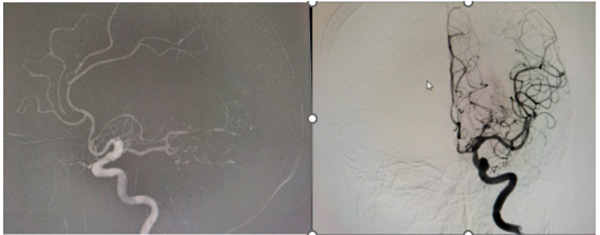

95岁女性患者,突发意识障碍,检查发现为大血管闭塞。家属抱着最后一搏的希望送至怀柔医院。卒中中心团队迅速评估后,认为尽管年龄极高,但仍有取栓机会。在麻醉科的精密护航下,介入团队凭借精湛的技术,成功取出血栓,打通了生命的关键通道。

91岁的男性患者,入院时已意识模糊,左侧肢体完全偏瘫,病情危重。团队同样没有放弃,果断实施取栓手术。手术成功的关键在于对病变血管的精准操作和对可能并发症的预判与规避。